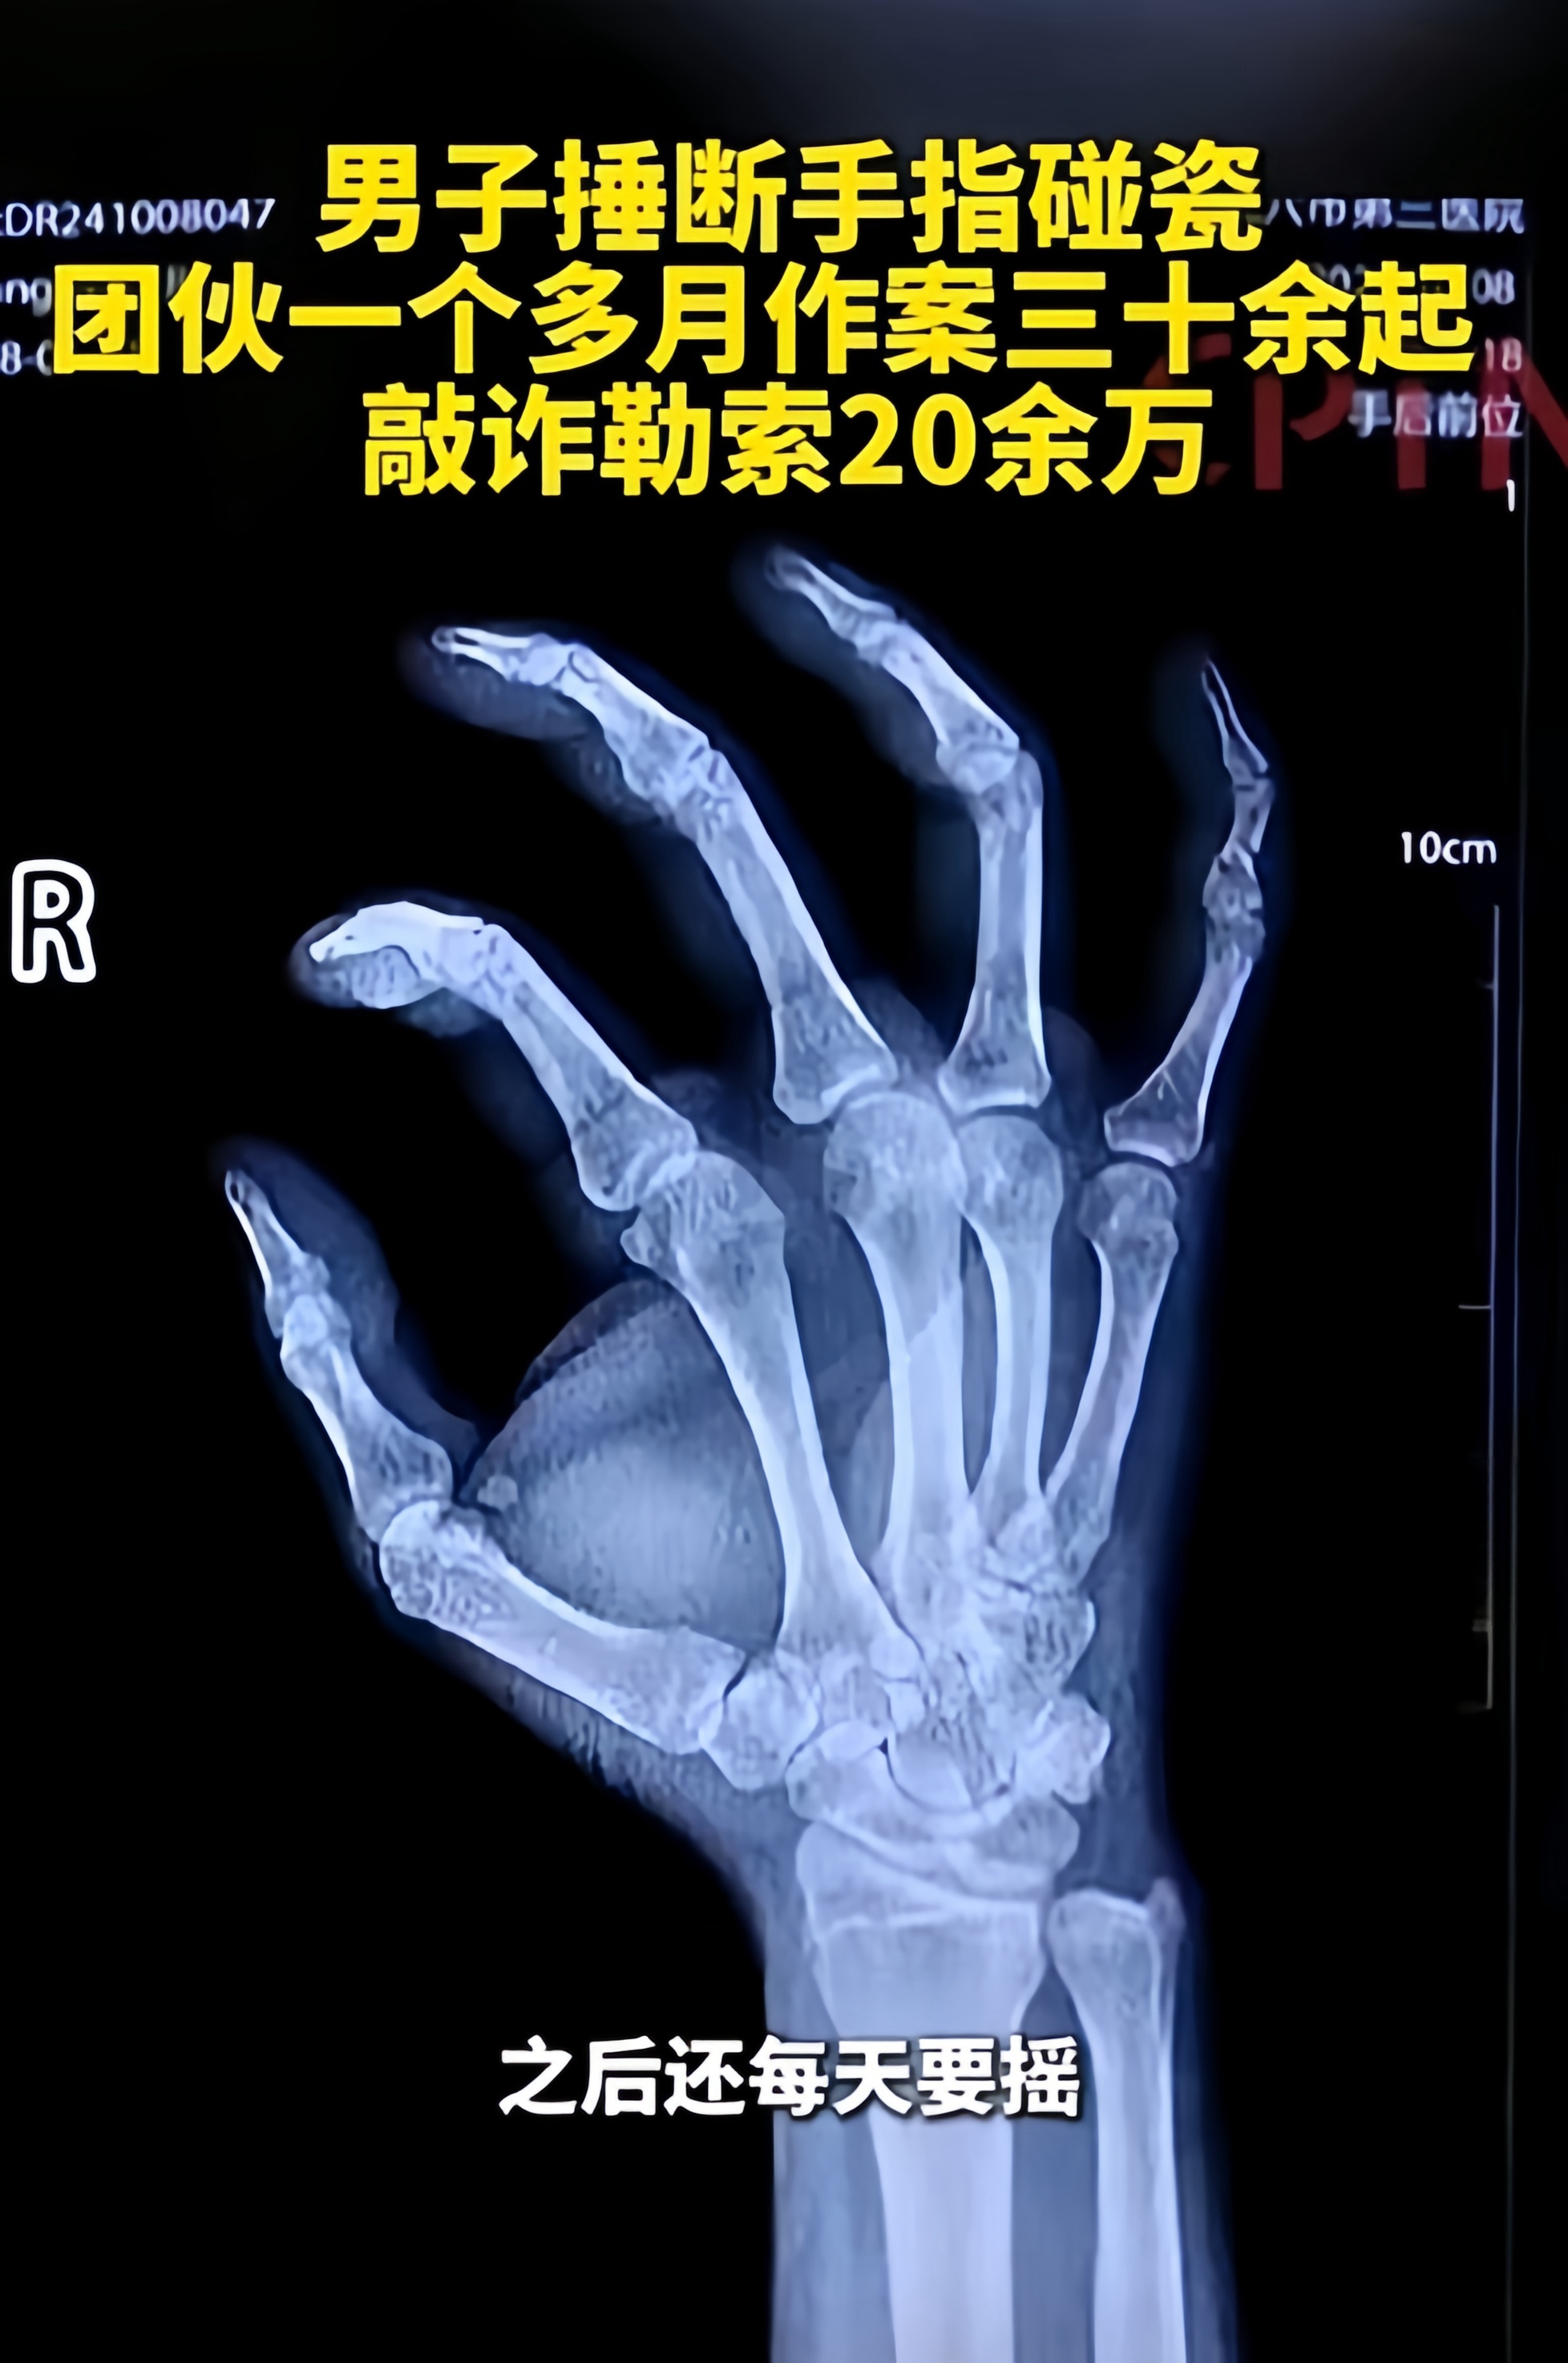

民警将黄某送往医院检查,发现其小指有旧伤,并非交通事故所致。这一检查结果给办案人员敲响了警钟。

经调查发现,黄某近期发生多起交通事故,其中多为小指受伤。

为了金钱,黄不惜对自己残忍。他用纱布包住小指后,用锤子将其打破。

每次折断手指他都要忍受巨大的痛苦,但在金钱的诱惑下,他选择了坚持这种疯狂的行为。